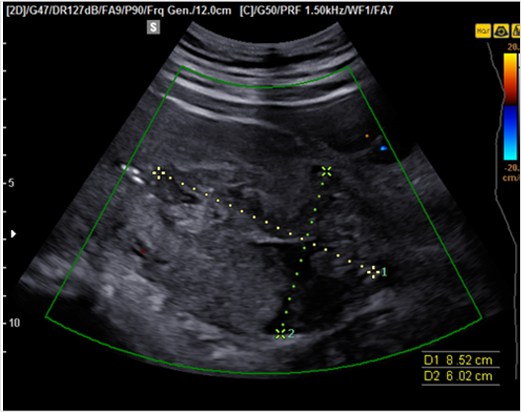

그림3. 자궁이완증. 자궁이 분만후에도 커져 있고 자궁강 내에 저에코성의 일정하지 않은 모양의 혈종이 있으며 컬러도플러에서 혈류가 관찰되지 않음.

자궁이완증분만 후 자궁수축이 원활하게 이루어 지지 않아 발생하는데, 자궁이 커져 있고, 질출혈이 있는 것이 특징이다. 초음파에서도 자궁이 늘어나 있고 자궁강내에 저에코성, 일정하지 않은 모양의 덩이가 보이면서 컬러도플러에서 혈류가 관찰되지 않는 혈종이 고여 있는 것으로 진단할 수 있다.